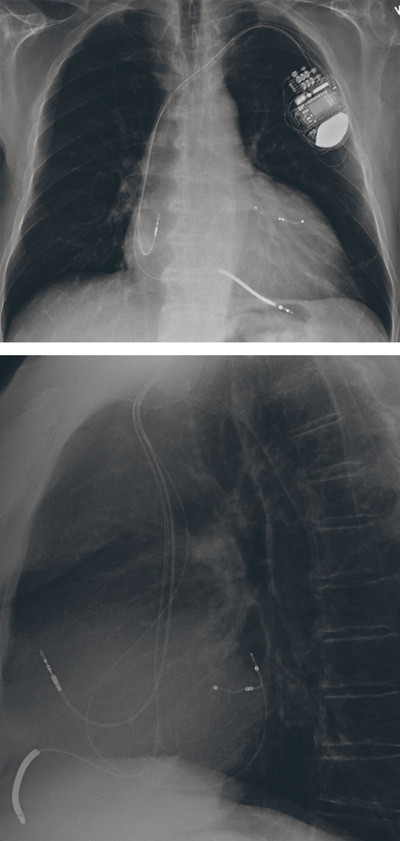

Et system med kardial resynkroniseringsbehandling implanteres ved at en pacemakerledning plasseres via sinus coronarius i en koronarvene over laterale del av venstre ventrikkel og en ledning endokardialt apikalt eller i interventrikulærseptum i høyre ventrikkel (15, 16). Ved simultan stimulering fra høyre og venstre elektrode oppnår man mekanisk resynkronisering av venstre ventrikkel. Hos pasienter med sinusrytme implanteres en ledning til høyre atrium for sensing av egenrytme og for å synkronisere AV-overledningen med biventrikulær pacing for ytterligere å øke den hemodynamiske effekten. Ventriklene må stimuleres kontinuerlig av pacemakeren simultant for å resynkronisere kontraksjonen og øke venstre ventrikkels ejeksjonsfraksjon. Ved alvorlige ventrikulære takyarytmier eller ved høy risiko for hjertestans kombineres pacemakersystem med innebygd kardioverter-defibrillator-funksjon (implantable cardioverter defibrillator, ICD ), da kalt CRT-D (fig 1). Et biventrikulært pacemakersystem uten innebygd kardioverter-defibrillator-funksjon kalles CRT-P.